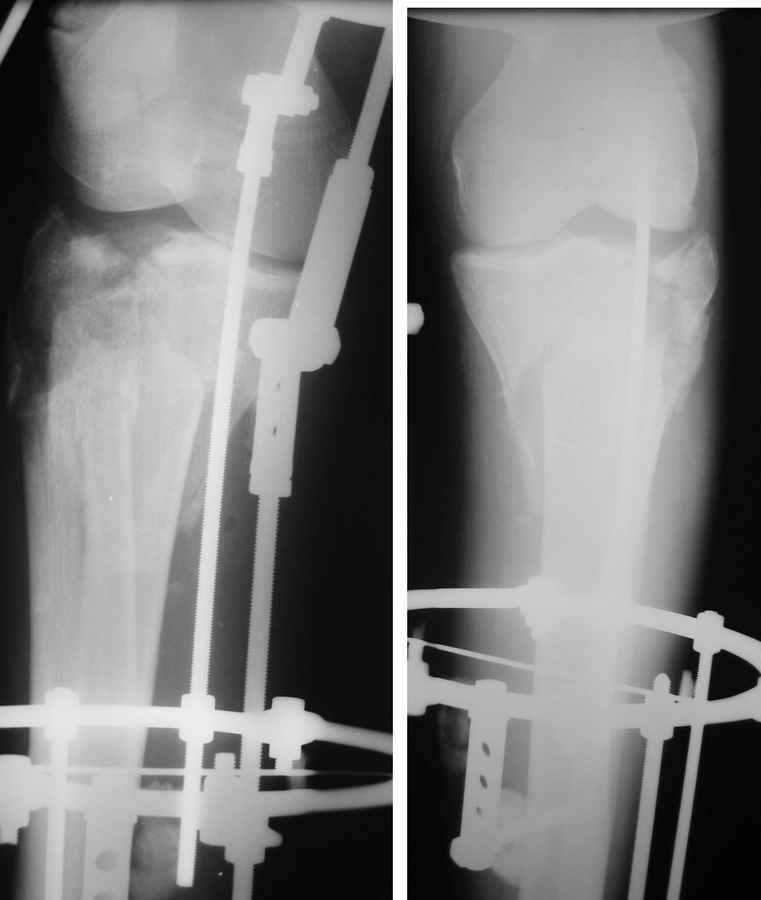

Очаг некроза 4 на 5 см по передней поверхности голени не оставил никакого варианта кроме внешнего остеосинтеза.

Но решили делать в 2 этапа. Первый - восстановить ось и дать костной крошке в проксимальном отделе консолидироваться.

Но по результатам первого этапа думаем дать пациенту попользоваться ногой. А там посмотрим.